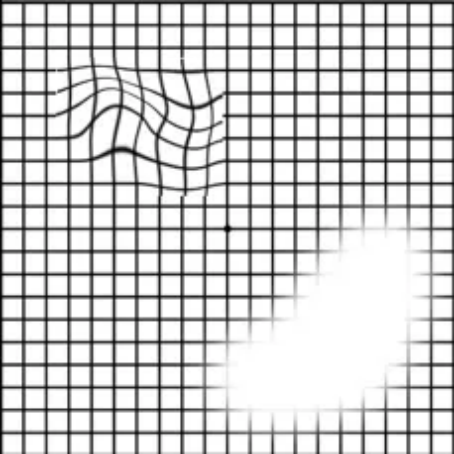

对于高风险人群,可以通过阿姆斯勒方格表观察视物是否变形:

看图测“黄斑病变”:

1. 如有老花或近视,需配戴原有的眼镜进行测试;

2. 把方格表放在视平线30厘米处,光线要清晰且平均;

3. 用手掌盖住左眼,右眼凝视方格表的中心黑点;

4. 重复以上步骤,检查左眼。

↑ 以上表格

你看到的是以下哪张图的样子?↓

图1

图2

图3

查看答案

图1:恭喜你,眼底黄斑正常!

图2或图3:眼底黄斑出现了问题!